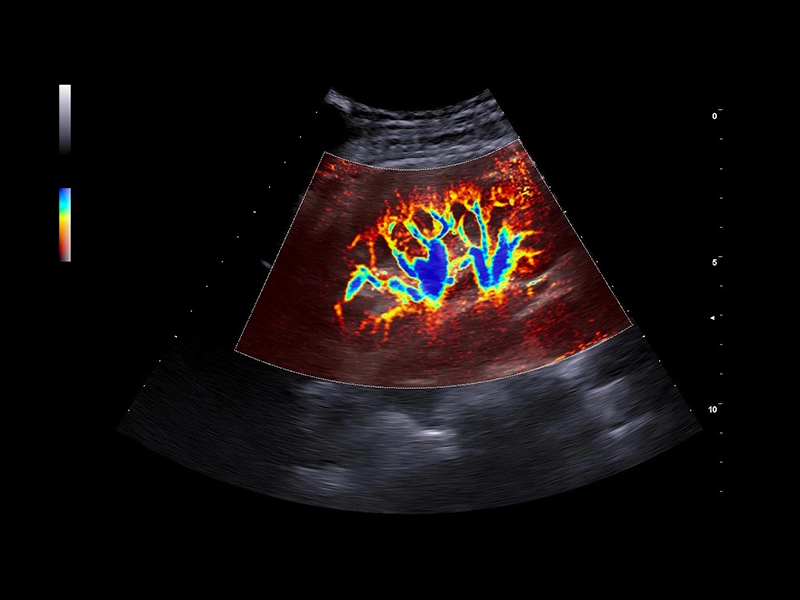

MyLab™9 Platform - Hemodynamics analysis using microV on kidney

MyLab™9 Platform - Hemodynamics analysis using microV on kidney